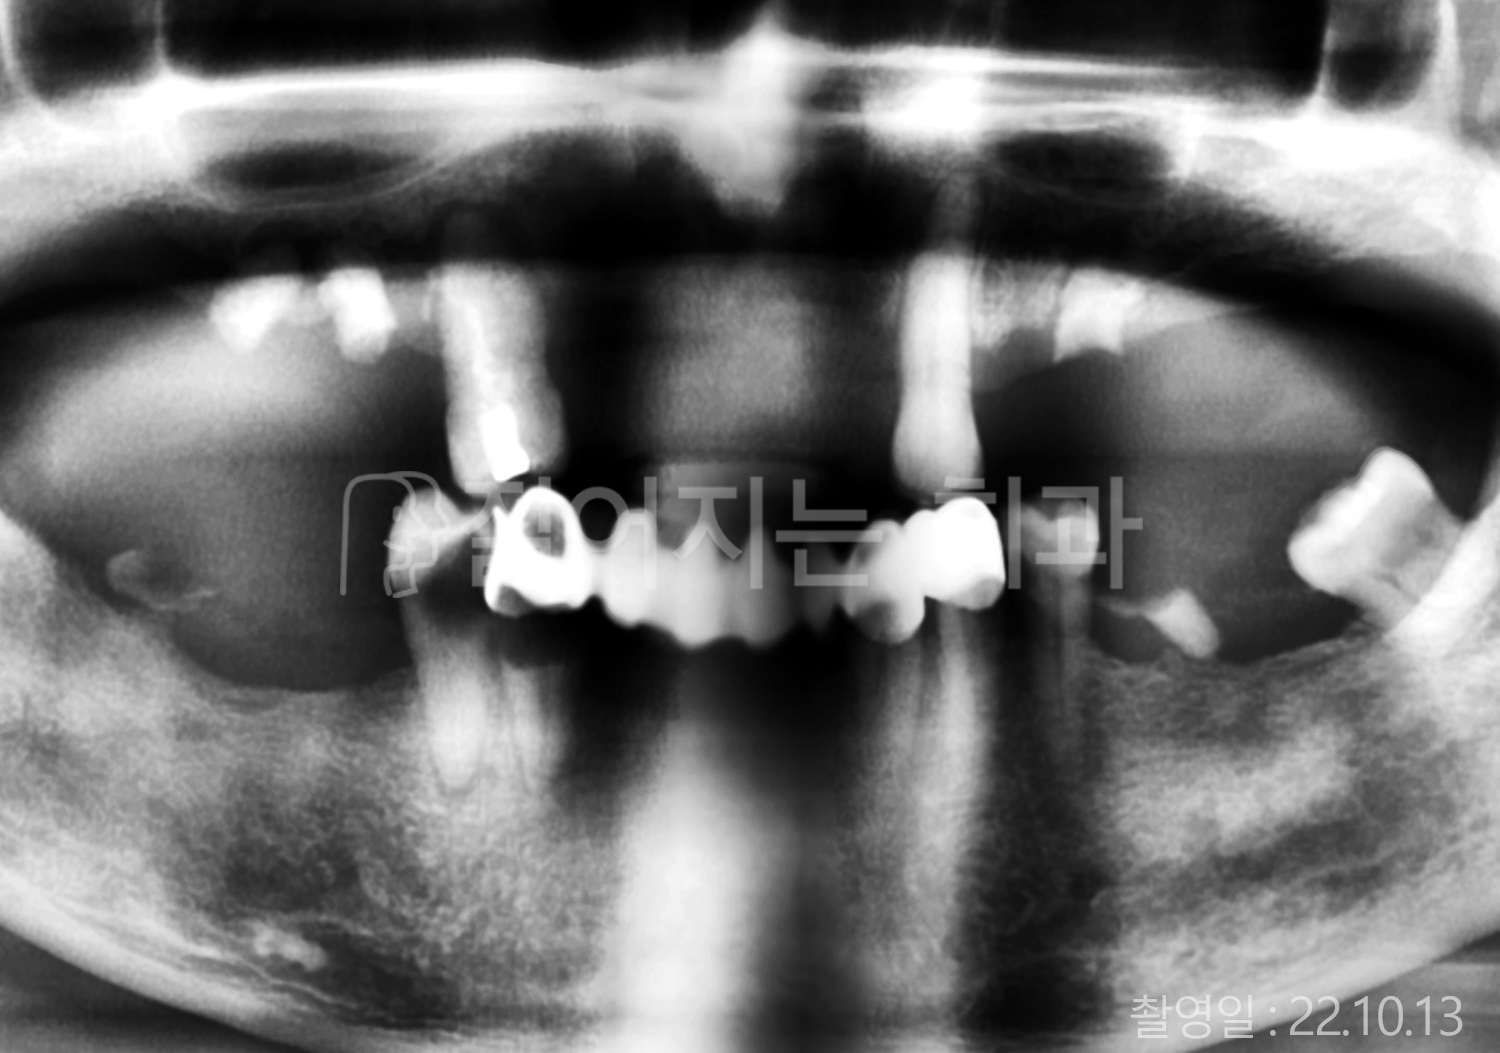

• 40대 전체치아 10개 이상 임플란트

• 70대 당뇨 전체치아 10개 이상 임플란트

• 60대 전체치아 10개 이상 임플란트

• 60대 고혈압, 당뇨, 고지혈증 전체치아 10개 이상 임플란트

• 50대 전체치아 10개 이상 임플란트

• 70대 고혈압, 당뇨 전체치아 10개 이상 임플란트

• 60대 고혈압 전체치아 10개 이상 임플란트

• 50대 고혈압, 당뇨, 고지혈증 전체치아 10개 이상 임플란트

• 60대 고혈압, 고지혈증 전체치아 10개 이상 임플란트